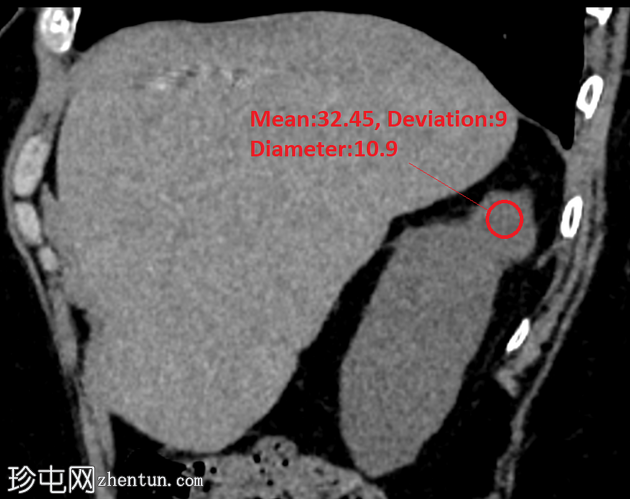

矢状位平扫

5.png

右肾后上极可见2.8 cm外生性强化病灶,提示肾细胞癌(RCC)。右肾静脉和下腔静脉通畅。未见明显局部淋巴结肿大。右肝叶可见高密度金属影。可见含脂肪的脐疝。

嗜铬细胞肾细胞癌 (chRCC) 约占肾脏恶性上皮肿瘤的 5%,常为偶然发现。该肿瘤血管丰富度中等,但病理上血管分布不明显,在所有影像学阶段的强化程度均低于肾皮质,肾实质期强化最为显著。